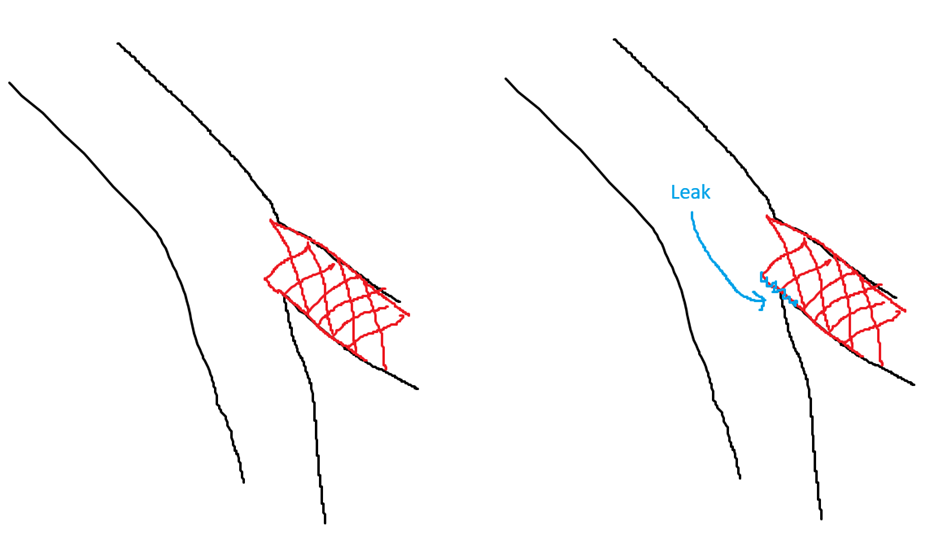

After diagnostic coronary angiogram, we proceeded to functional study of the D2 branch using 7Fr EBU 3.75 which confirmed functional significance with a RFR value of 0.75 and we proceeded with PCI. Ostium to proximal D2was pre-dilated with non-compliant 2.0 & 2.5 as well as cutting 3.0 balloon with recoil noted on angiogram after balloon inflation.IVUS imaging revealed underlying heavily calcified lesion and a sized-down 3.0 Shockwave balloon was deployed hoping to crack the calcium.Unfortunately the situation was complicated by perforation at very proximal D2 after Shockwave balloon inflation. The leak was localized at D2, yet balloon tamponade failed to seal the leak and hence 3.0 cover stent was deployed at D2 which seemingly sealed the leak.With a hope to reshape/align the carina, sequential dilatation of ostium D2 followed by kissing balloon inflation (KBI) with NC 3.5 in LAD & NC 3.0 in D2 was done. Unfortunately bleeding re-emerged after KBI, possibly due to crumpling of the proximal part of cover stent with possible extension of perforation into LAD. Thereafter the procedure became difficult as multiple balloon tamponade attempts in LAD/D2 failed to seal the leak. We ran out of options and had to deploy two cover stents in p-mLAD in order to control the leak. After stenting the LAD the leak improved but still some slow leak remained and we decided to go for reverse heparinization. Eventually the leak was much reduced to a minimal extent.

This case demonstrated how our team tackled an unfortunate PCI complication of diagonal branch perforation.

On hindsight, protruding less of the diagonal cover stent or stopping the procedure right after deploying diagonal cover stent may lead to a better outcome, hence the title "When Less Is More".